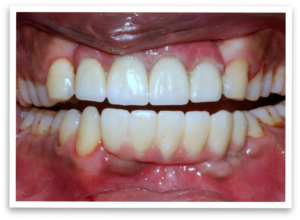

Following the implant placement, a healing period of six months was crucial. Once healed, the prosthetic phase began. Through collaboration with our skilled lab technicians, we created a customized solution. A Paulo Malo bridge was chosen for the upper jaw, offering exceptional strength and aesthetics. The lower jaw received a screw-cement retained prosthesis, ensuring a secure and comfortable fit.

The final outcome was truly remarkable. The patient could now confidently chew, speak, and most importantly, smile broadly! This transformation not only improved his oral health and function, but also brought back the confidence he thought he had lost after the accident. His story is a testament to the power of modern dental techniques and the unwavering spirit of patients seeking a brighter future.